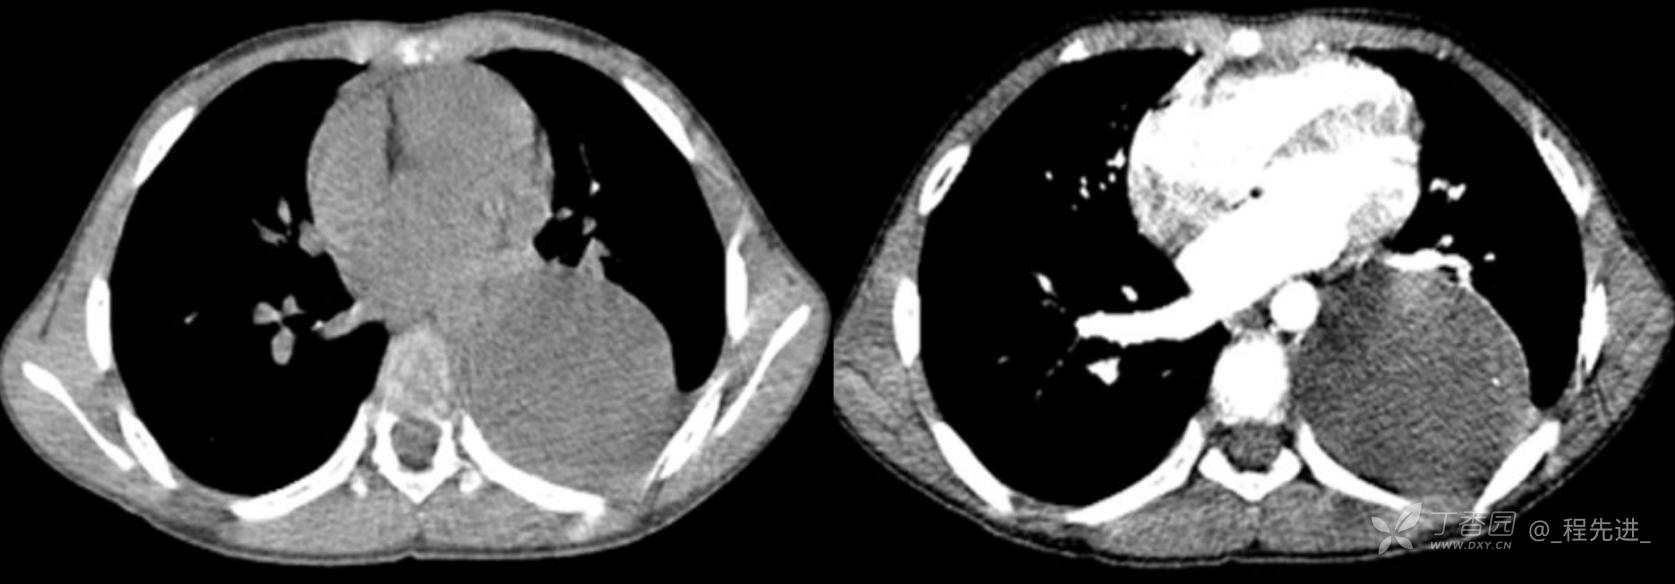

11月特别精彩病例|胸片示“左侧胸腔包裹性积液”,CT增强你诊断啥?【病理已公布】

呱呱叫了 等 3 位达人已点赞男,11岁,患儿因其爷爷近期在我院诊断“肺结核”,于外院行结核筛查,胸片示“左侧胸腔包裹性积液”,近期无咳嗽、发热、纳差、盗汗、乏力、胸痛、胸闷、气促不适,精神反应可,为求明确“左侧胸腔包裹性积液”病因,遂来我院门诊就诊,门诊以“胸腔积液查因”收住入院。发病以来,精神尚可食欲如常,大便如常,小便量如常,体重无明显变化

各项实验室检查均正常